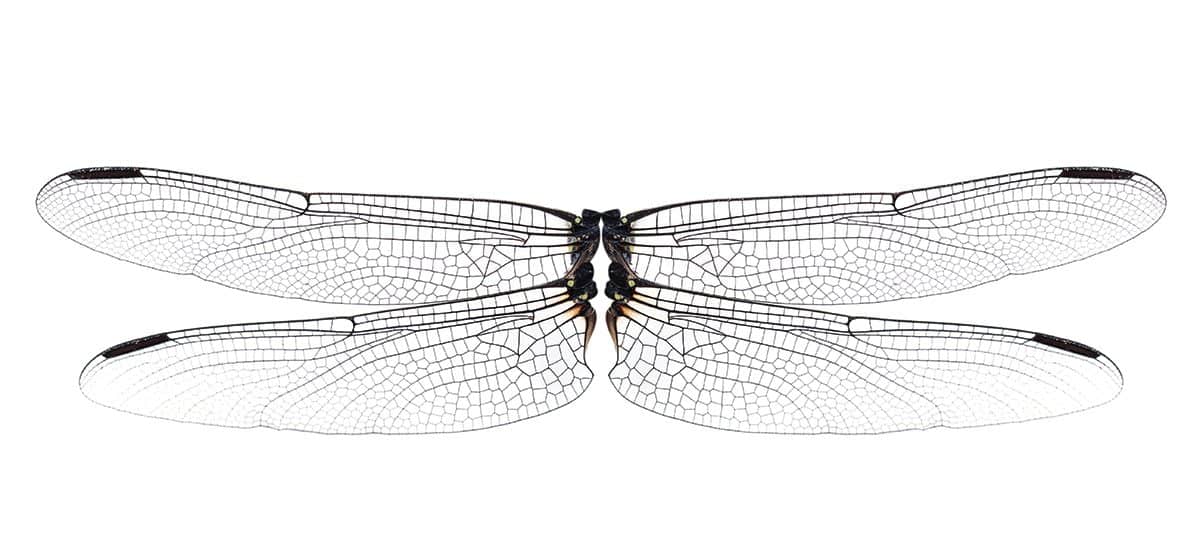

Et si on s’inspirait des ailes d’insectes pour lutter contre les infections nosocomiales?

Pour concevoir des matériaux plus sécuritaires, une équipe montréalaise se tourne vers… les libellules et les cigales ! Et plus précisément vers leurs ailes, qui sont naturellement antibactériennes. « Elles sont couvertes de minuscules picots, sorte de nanoclous qui tuent les bactéries par contact physique », a expliqué Dao Nguyen, chercheuse à l’Institut de recherche du Centre universitaire de santé McGill, au cours d’un symposium de l’Initiative interdisciplinaire en infection et immunité de McGill en juin dernier. Plusieurs équipes s’intéressent à cette approche « mécanique », alors que les biofilms, enchâssés dans une gangue collante et protectrice, ont une capacité extrême à résister au système immunitaire. Ces communautés de microorganismes sont aussi de 500 à 5 000 fois plus résistantes aux traitements antibiotiques que les bactéries de même nature isolées.